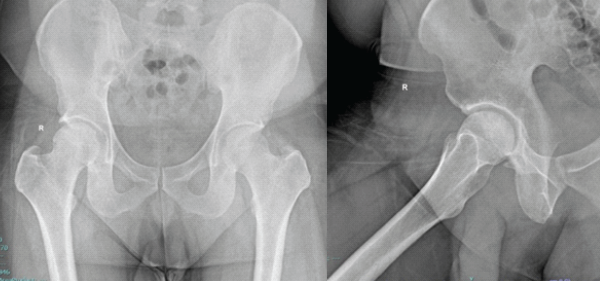

MRI scan of the right hip demonstrated an osteochondral defect of the femoral head with associated subchondral edema (Fig. 3a and b). There were no obvious signs of avascular necrosis (AVN) of the femoral head.

Figure 3: (a and b) Magnetic resonance images showing altered signal intensity in the anterosuperior aspect of the right femoral head.